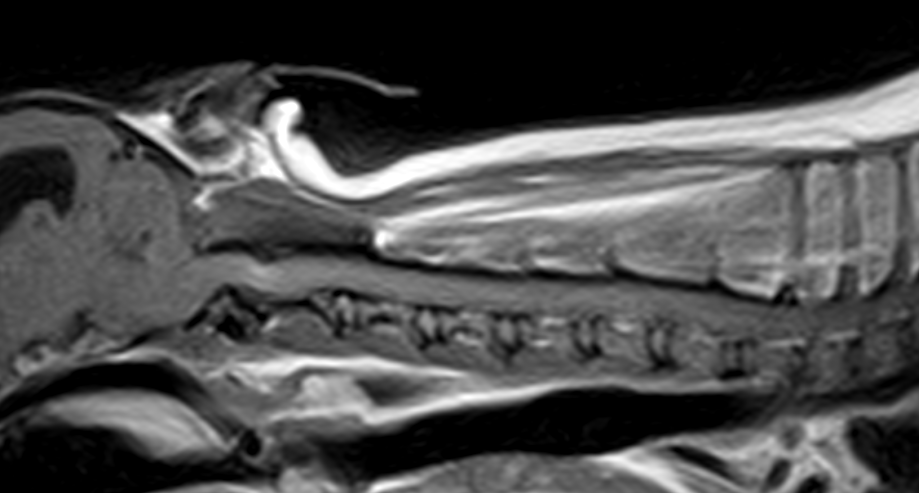

かかりつけの先生から、3歳のチワワが悲鳴をあげて、首を痛がり、歩けなくなっているので、すぐにMRIを撮って原因を調べて必要があれば手術をして欲しいと連絡がありました。すぐに来院され、神経学的な検査とCT・MRIを実施したところ、環椎と軸椎の不安定症が原因とわかりました。すぐに頸部にコルセットを着用し、状態を安定化しました。翌日には小康状態を得ていたので、環軸固定術を行いました。

手術は1.5mmのチタンスクリューを第2頚椎に挿入し、亜脱臼している軸椎を腹側に牽引します。その後、関節面を超音波骨メスにより軟骨を掻爬し、骨面を露出、上腕骨より海綿骨を採取し、関節面に移植します。その後、経関節にポジティブチタンピンを2本、環椎に2本刺入します。

これらをチタンメッシュによりインプラントを一括セルフロック状態とさせます。さらにごく少量の骨セメントでインプラントを固定します。

このチタンメッシュの役割として、セメントの重合熱から骨のオーバーヒートから守る。感染のリスクのあるセメントの消費量を少なくする。関節固定の強度を担保する。また、ステンレスを使わない理由としては、金属アーチファクトが少ないので、術後にMRIの撮影が可能。ステンレスより熱伝導率が悪いため、セメントの重合熱を骨に伝えにくいといったメリットがあると考えています。

術後は一切の疼痛が消失し、徐々に起立できるようになってきています。